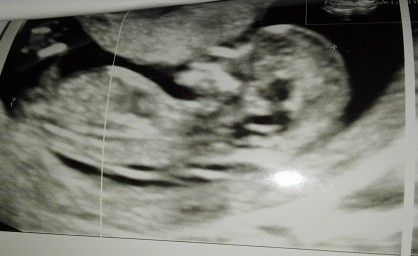

Ciaooo qualcuna ha sentito parlare del metodo Ramzi? A voi ci ha azzeccato o ha sbagliato? Vi metto una foto dell’eco interna a 7+3 “dovrebbe” essere maschio secondo la teoria o sbaglio io a vedere? Altra domandina: l’11 ho fatto il dna fetale (con...